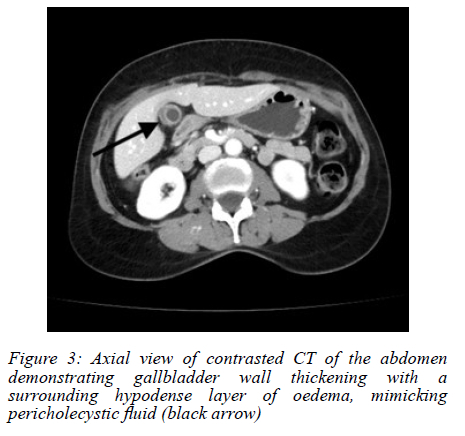

An abdominal ultrasound (AUS) showed a possible stone in the gallbladder neck, with a thickened and oedematous gallbladder wall (Figure 1). No masses were noted on sonar. The history of loss of weight was further investigated. A colonoscopy was performed, which was normal. A computed tomography (CT) scan did not show any concerning features, and a thickened gallbladder wall was once again visualised (Figure 2, 3).

Radiologically, CT and ultrasound findings are nonspecific, ranging from wall thickening to mass-like lesions with necrosis or calcification.68 These features overlap significantly with gallbladder malignancy or chronic inflammation,6,8 making preoperative diagnosis challenging. Radiologic "red flags" suggesting TB over carcinoma include gallbladder wall with necrotic core, multiple flecked calcifications, broad-based micronodular lesions, pericholecystic oedema, and necrotic lymph nodes.6 Consequently, in the absence of systemic TB features or pulmonary symptoms, most diagnoses hinge on postoperative histopathology, where necrotising granulomas with or without acid-fast bacilli confirm the diagnosis.9